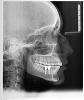

dimina Опубликовано 5 июня, 2013 Поделиться Опубликовано 5 июня, 2013 (изменено) Два года назад мне подняли брекет-ситемой провисащий верхний ряд под 2 импланта на нижней челюсти(т.к. верхняя челюсть провилса до нижней в этом месте,зубы уже давно отсутвовали). Всё благополучно выровняли,подняли,но после того как установили штифты(временных коронок мне не ставили) - за 3-4 мес зубной ряд опять опустился,не так сильно как раньше,но место под импланты значительно умеьшилось. Ортодонт только потом поняла,что не предусмотрела это. После того как накрутили коронки начались болевые ощущения - в основном под одним имплантом/коронкой, сделали снимок -хирург никак аномалий со своей стороны не увидел. Отправил на пришлифовку коронки к ортопеду, сошлифовали эту коронку как-бы под углом,не плоско, так оставили, сказали больше спиливать уже не можем, ходите -привыкайте. Походила 2-3 недели,пошла опять к ортодонтам за консультацией - ортодонты пришлифовали мои родные зубы под удобный прикус. Ощущения вначале шлифовки были комфортные,что всё на место стало, но видимо где-то переборщили в процессе - стало еще хуже и дискомфортнее,чем первоначально. Ортодонт предположила,что прикус занизила и нужно теперь наборот поднимать - при этом ни снимков ТРГ, ни общего никто не отправлял сделать.Далее ортодонт экспериментировала со мной так: я жевала ватные турундочки, чтобы она определила ествественное положение челюсти и по этому положению изготовили каппу силиконовую. С ней я недели 2 проходила + сделали мне накладку на один врехний зуб (который над проблемной коронкой был) - её идеей было ,что все зубы дорастут пока я хожу с накладкой до нужной высоты (высоты накладки) .Тоже проходила какое-то время - никуда зубы не доросли,а наоборот утопились под десну (нижние последние).В итоге она предложила , единственный выход - снова носить брекет-систему и заново всю челюсть подгонять,а потом менять эти коронки в процессе.После этого я обратилась за консультацией к ортопеду(считается один из лучших в городе),т.к. ходить 2 года еще с брекетами не хотелось. Сделала снимок ТРГ,ОПТГ (прилагается) - из симптомов добавились щелканье челюсти при усиленном жевании на тот момент (капу перестала носить,тольео с накладкой ходила).Ортопед раскрутил коронки, подшлифовал их ровно, сделал поуже,чтобы увеличить расстояние между имлантами и своими зубами,спилил накладку ортодонта, наблюдает.На данный момент имею:- ощущение нехватки высоты на левой челюсти,где были сошлифованы последние зубы под капу,(теперь там зазор в 2 мм между верхним и нижним последними) и ощущение напряжения и скованности челюсти/мыщц - преимущественно слева. При усиленном жевании - щелканье . До пришлифовки и проч. манипуляций такого ощущения не было . Заранее всем спасибо за коментарий и ответ!Снимки до спила накладки последние : http://s017.radikal.ru/i407/1306/d0/ed809aaaae0ct.jpg Изменено 5 июня, 2013 пользователем dimina Ссылка на комментарий